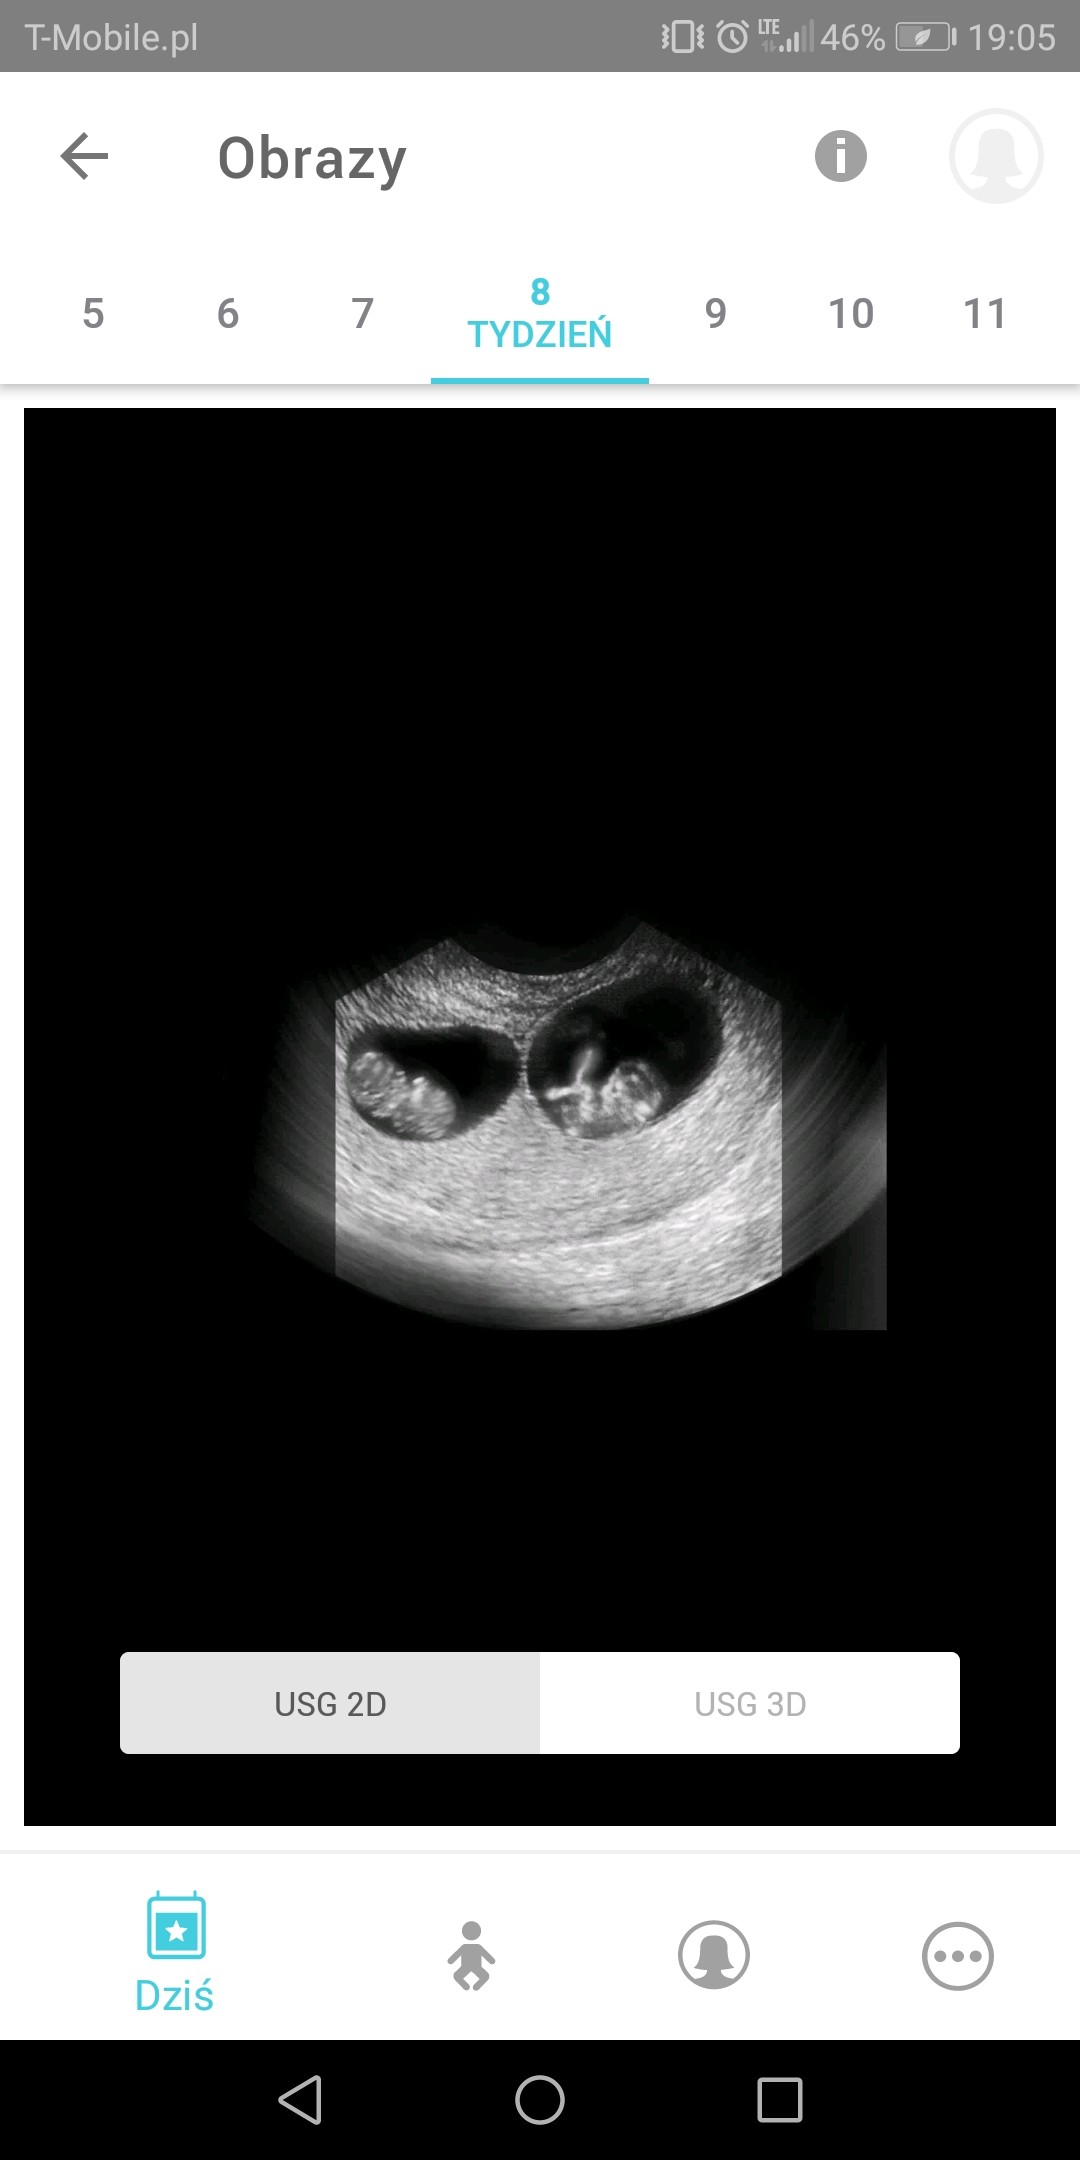

uznajmy ze jednak sobie wmawiam ale zszokowalo mnie to wtedy i mysle juz od czwartku nad tym. Caly internet przepatrzylam w zdjeciach blizniat z usg

Boze nie strasz widzialam 2 takie czarne ale maleHahahadalabys rade

Ale na pewno bedzie jedenmoze po prostu to tak wygląda

tak chyba wygladaja według ciaza +

Zobacz załącznik 1105952